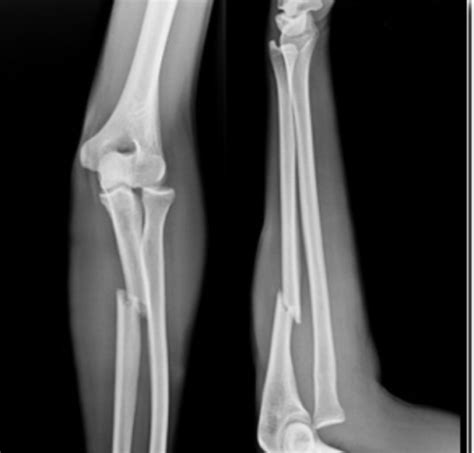

但有时候价格高并不一定看得更清楚。就拿骨折来说,X线就比磁共振要看得清楚的多,选择何种检查还是要依据病人的具体情况而定!看看下面这个X线片,是不是瞎子都可以看出来是骨折了!